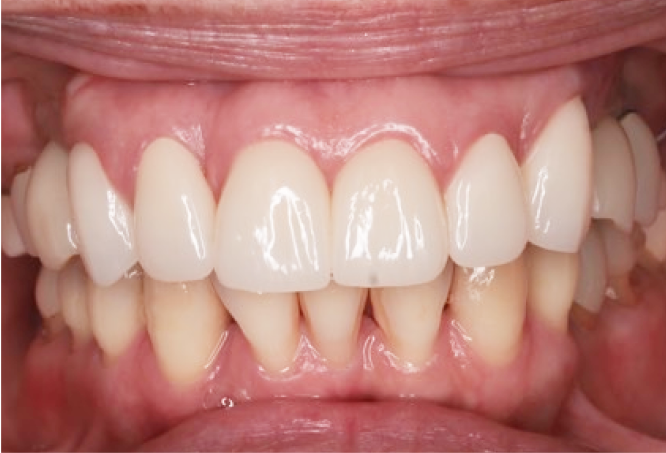

症例

Before

After